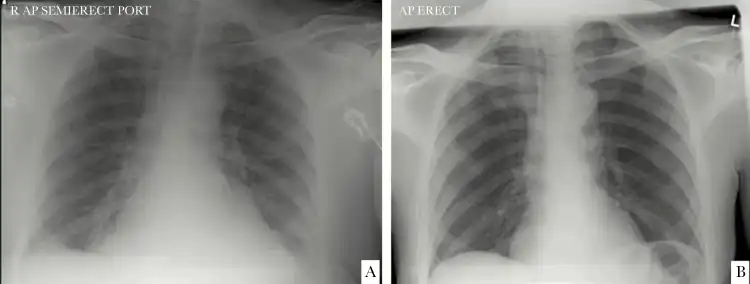

a)Chest x-ray from individual at time of CoV-HKU1 diagnosis b) chest x-ray 1-year before -

HCoV-HKU1 was first detected in January 2004, in a 71-year-old man who was hospitalized due to acute respiratory distress syndrome and radiographically confirmed bilateral pneumonia. The man had recently returned to Hong Kong from Shenzhen, China.[2][9]